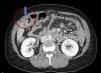

En la analítica sanguínea presentó leucocitosis de 13000/mm3 y elevación de reactantes de fase aguda (proteína C reactiva, 12mg/dl y fibrinógeno, 500). La ecografía abdominal (fig. 1) describía una hernia de Spiegel que contenía el apéndice cecal con cambios inflamatorios periapendiculares en su interior, y el tac (fig. 2) confirmó la localización herniaria al nivel de la aponeurosis de Spiegel derecha, con presencia del apéndice cecal en su interior y cambios inflamatorios de la grasa preperitoneal.